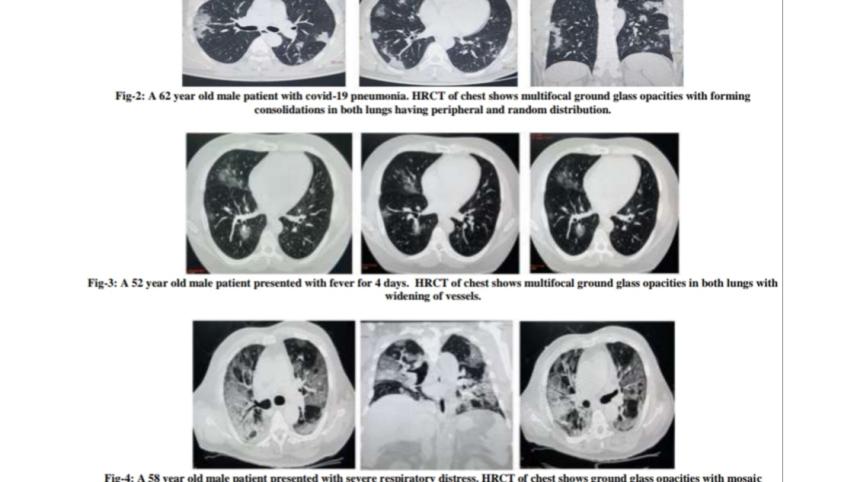

৫১ জন সন্দেহভাজন কোভিড-১৯ রোগীর ওপর সংশ্লিষ্ট চিকিৎসকের অনুমতি সাপেক্ষে এই গবেষণা চালানো হয়েছে। তাদের লক্ষণ ছিল এবং একই সঙ্গে আরটি-পিসিআর এবং বুকের সিটি স্ক্যান করিয়েছেন।

এই গবেষণা নারী-পুরুষ উভয়ের ওপরেই চালানো হয়। রোগীদের গড় বয়স ছিল ৪৫ বছরের মধ্যে এবং উপসর্গের সময়সীমা ছিল সাড়ে তিন থেকে পাঁচ দিন।

এই রোগীদের লক্ষণ ছিল জ্বর, কাশি ও বুক ব্যথা। প্রায় সবারই সিটি স্ক্যান পরীক্ষায় রোগের উপস্থিতি পাওয়া যায়। এসময় কারও কারও আরটি-পিসিআরের প্রথম নমুনা পরীক্ষার ফলাফল ‘নেগেটিভ’ এসেছে। কিন্তু তিন-চারদিন পরের নমুনা পরীক্ষার ফলাফল এসেছে ‘পজিটিভ’। এভাবে কোভিড লক্ষণ যুক্ত সন্দেহভাজন রোগীদের মধ্য থেকে ২১ জনের ‘পজিটিভ’ এবং ৩০ জনের ‘নেগেটিভ’ রিপোর্ট আসে।

এই গবেষণায় দেখা গেছে, সিটি স্ক্যানে সঠিক ফলাফলের সংবেদনশীলতা ৯৫ দশমিক ৪৫ শতাংশ এবং প্রথম নমুনায় আরটি-পিসিআরের সংবেদনশীলতা ৮৬ দশমিক ৩৬ শতাংশ।